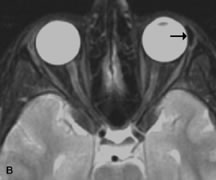

Metastatic Tumors

Breast carcinoma metastatic to the orbit has been demonstrated to be hypointense to the surrounding orbital fat on T1-weighted studies and hyperintense on T2-weighted images and has an affinity to the extraocular muscles (Fig. 20).50,64 The MRI characteristics of prostate carcinoma metastatic to the orbit have been described as involving the greater and lesser wing of the sphenoid, orbital roof, and optic canal. Diffuse bone hypertrophy with isointense or slightly hyperintense tissue on T1-weighted images represents the osteoblastic carcinomatous bone infiltration. Contrast enhancement is variable on T1-weighted and fat-suppressed images.65

Fig. 20. A. T1-weighted MR scan demonstrates nodular enlargement of both medial rectus muscles (arrows). B. T1-weighted fat-suppressed contrast-enhanced scan confirms the presence of small metnstatic deposits within the muscles (open arrows).